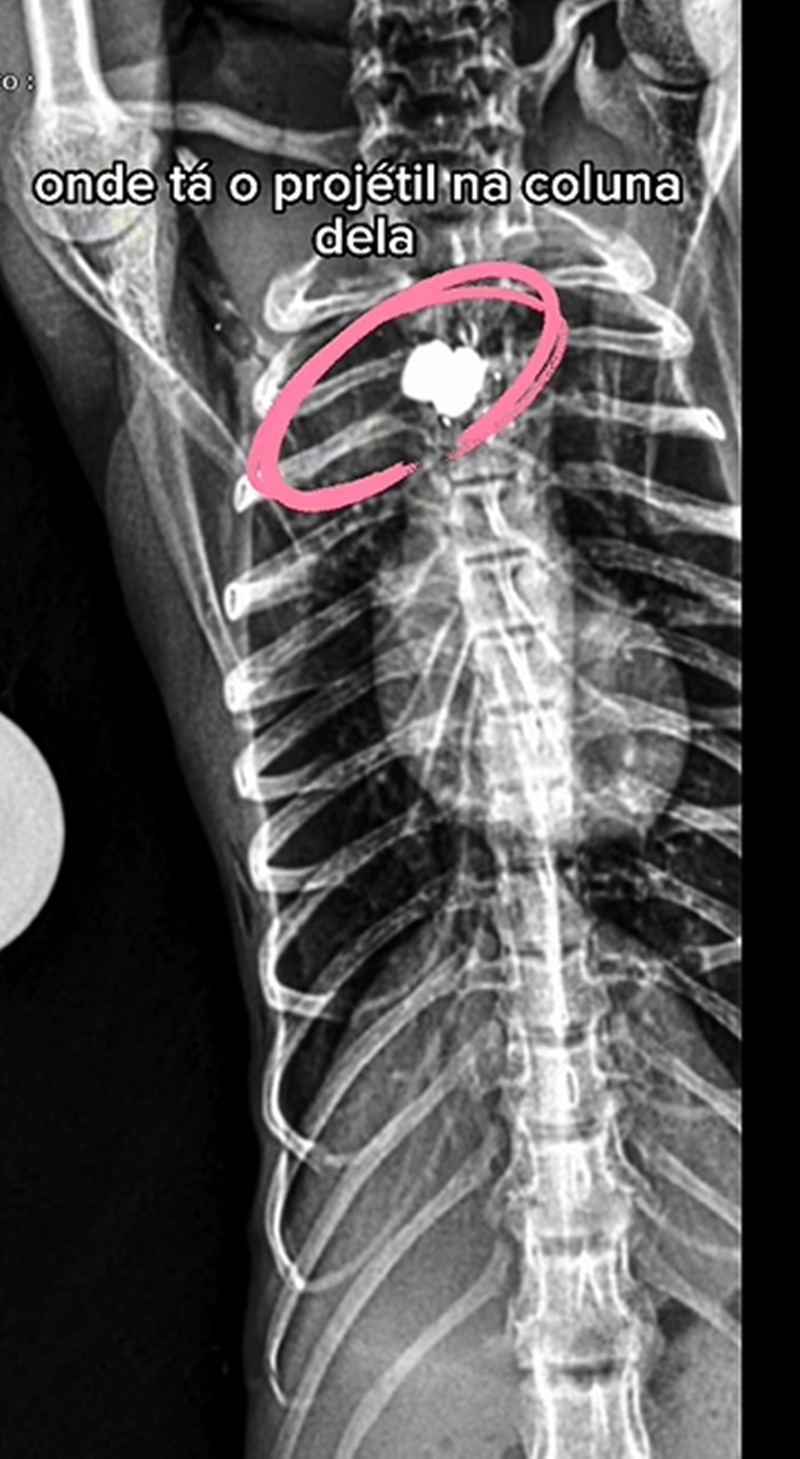

A macaquinha foi levada ao Instituto Vida Livre, onde recebeu os primeiros socorros e passou por exames iniciais. Ela aguarda cirurgia para retirada da bala, que está alojada na coluna. O tiro atingiu o ombro.

Em outra publicação, o instituto destacou que a macaca segue em tratamento e passou pelos exames de imagem (ultrassonografia e radiografia). Neles, foi possível entender a posição exata da bala em sua coluna.